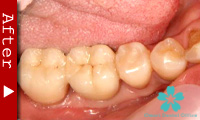

歯のない部分が広い場合

臼歯が失われた場合、従来は取り外し式の部分入れ歯で咬合機能を回復させてきました。

これに対し、インプラントなら天然歯と同様の感覚の”固定式”人工歯を入れることができます。